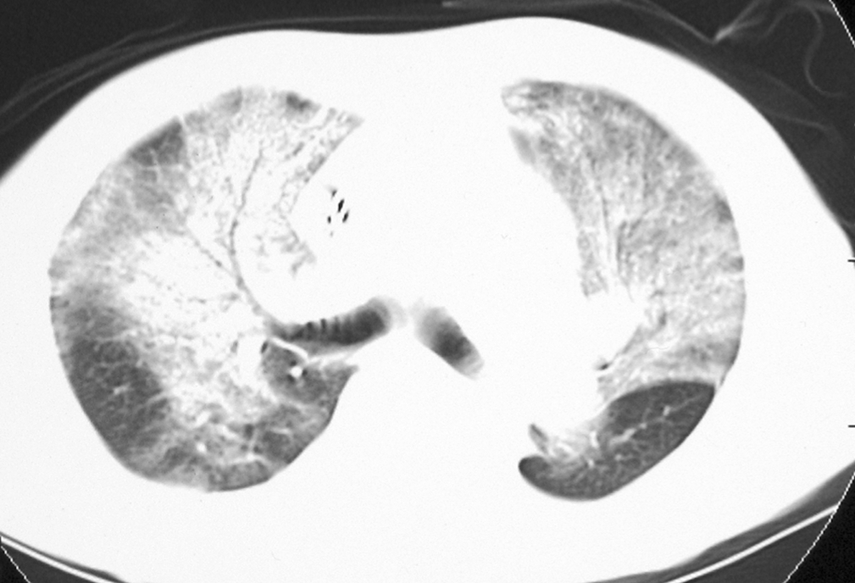

ARDS発症時の胸部CT像

両側に気管支透亮像を伴った肺胞性~すりガラス様浸潤影がみられる。CXRではびまん性にみえるが、CTでは正常部やそれに近い部分もある。